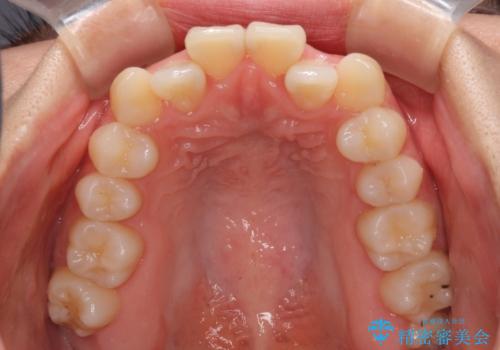

- 前歯のクロスバイトが気になり、インビザラインによる矯正治療を希望して来院された患者様です。

上顎側切歯(上の真ん中から2番目の歯)が舌側転位している場合、インビザラインでは仕上げきれないことが多く、更には無理して動かそうとすると歯髄壊死を起こすリスクが高いと言われています。

インビザラインで歯列を移動する前に、上顎前歯をワイヤー矯正で整え、その後上下歯列をインビザラインにて矯正治療を行うこととしました。

舌側転位している側切歯特有の、切縁の位置が不揃いであったり、根元が内側に引っ込んだ状態であったりという、インビザライン独特の仕上がりになることなく、きれいに整った歯列とすることができました。